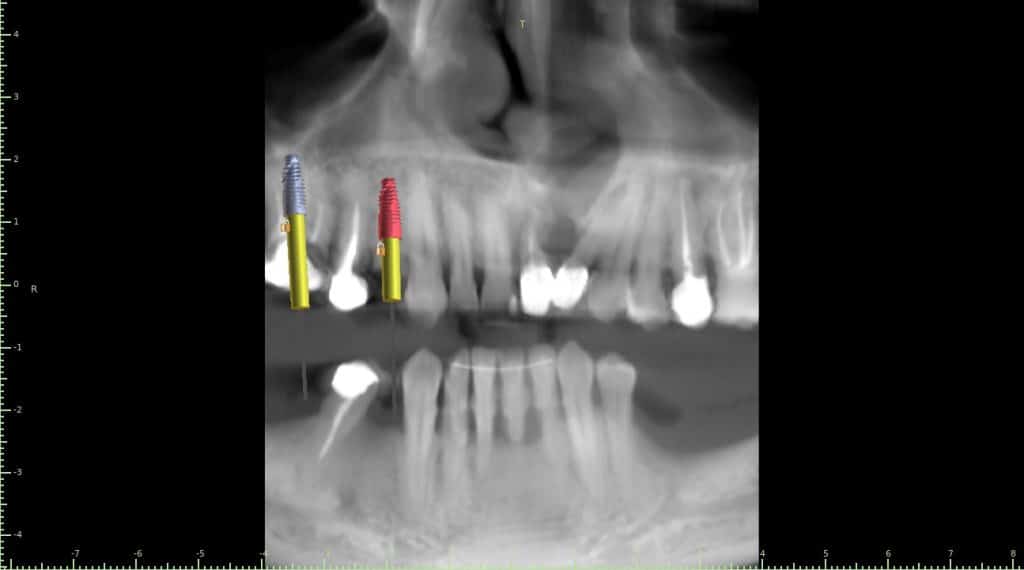

Case of the day where i extracted the 34-35-36 and an immediate placement of 2 implants in the 34-36 sites

sticky bone grafting GTO by osteobiol was used with straumann xenograft